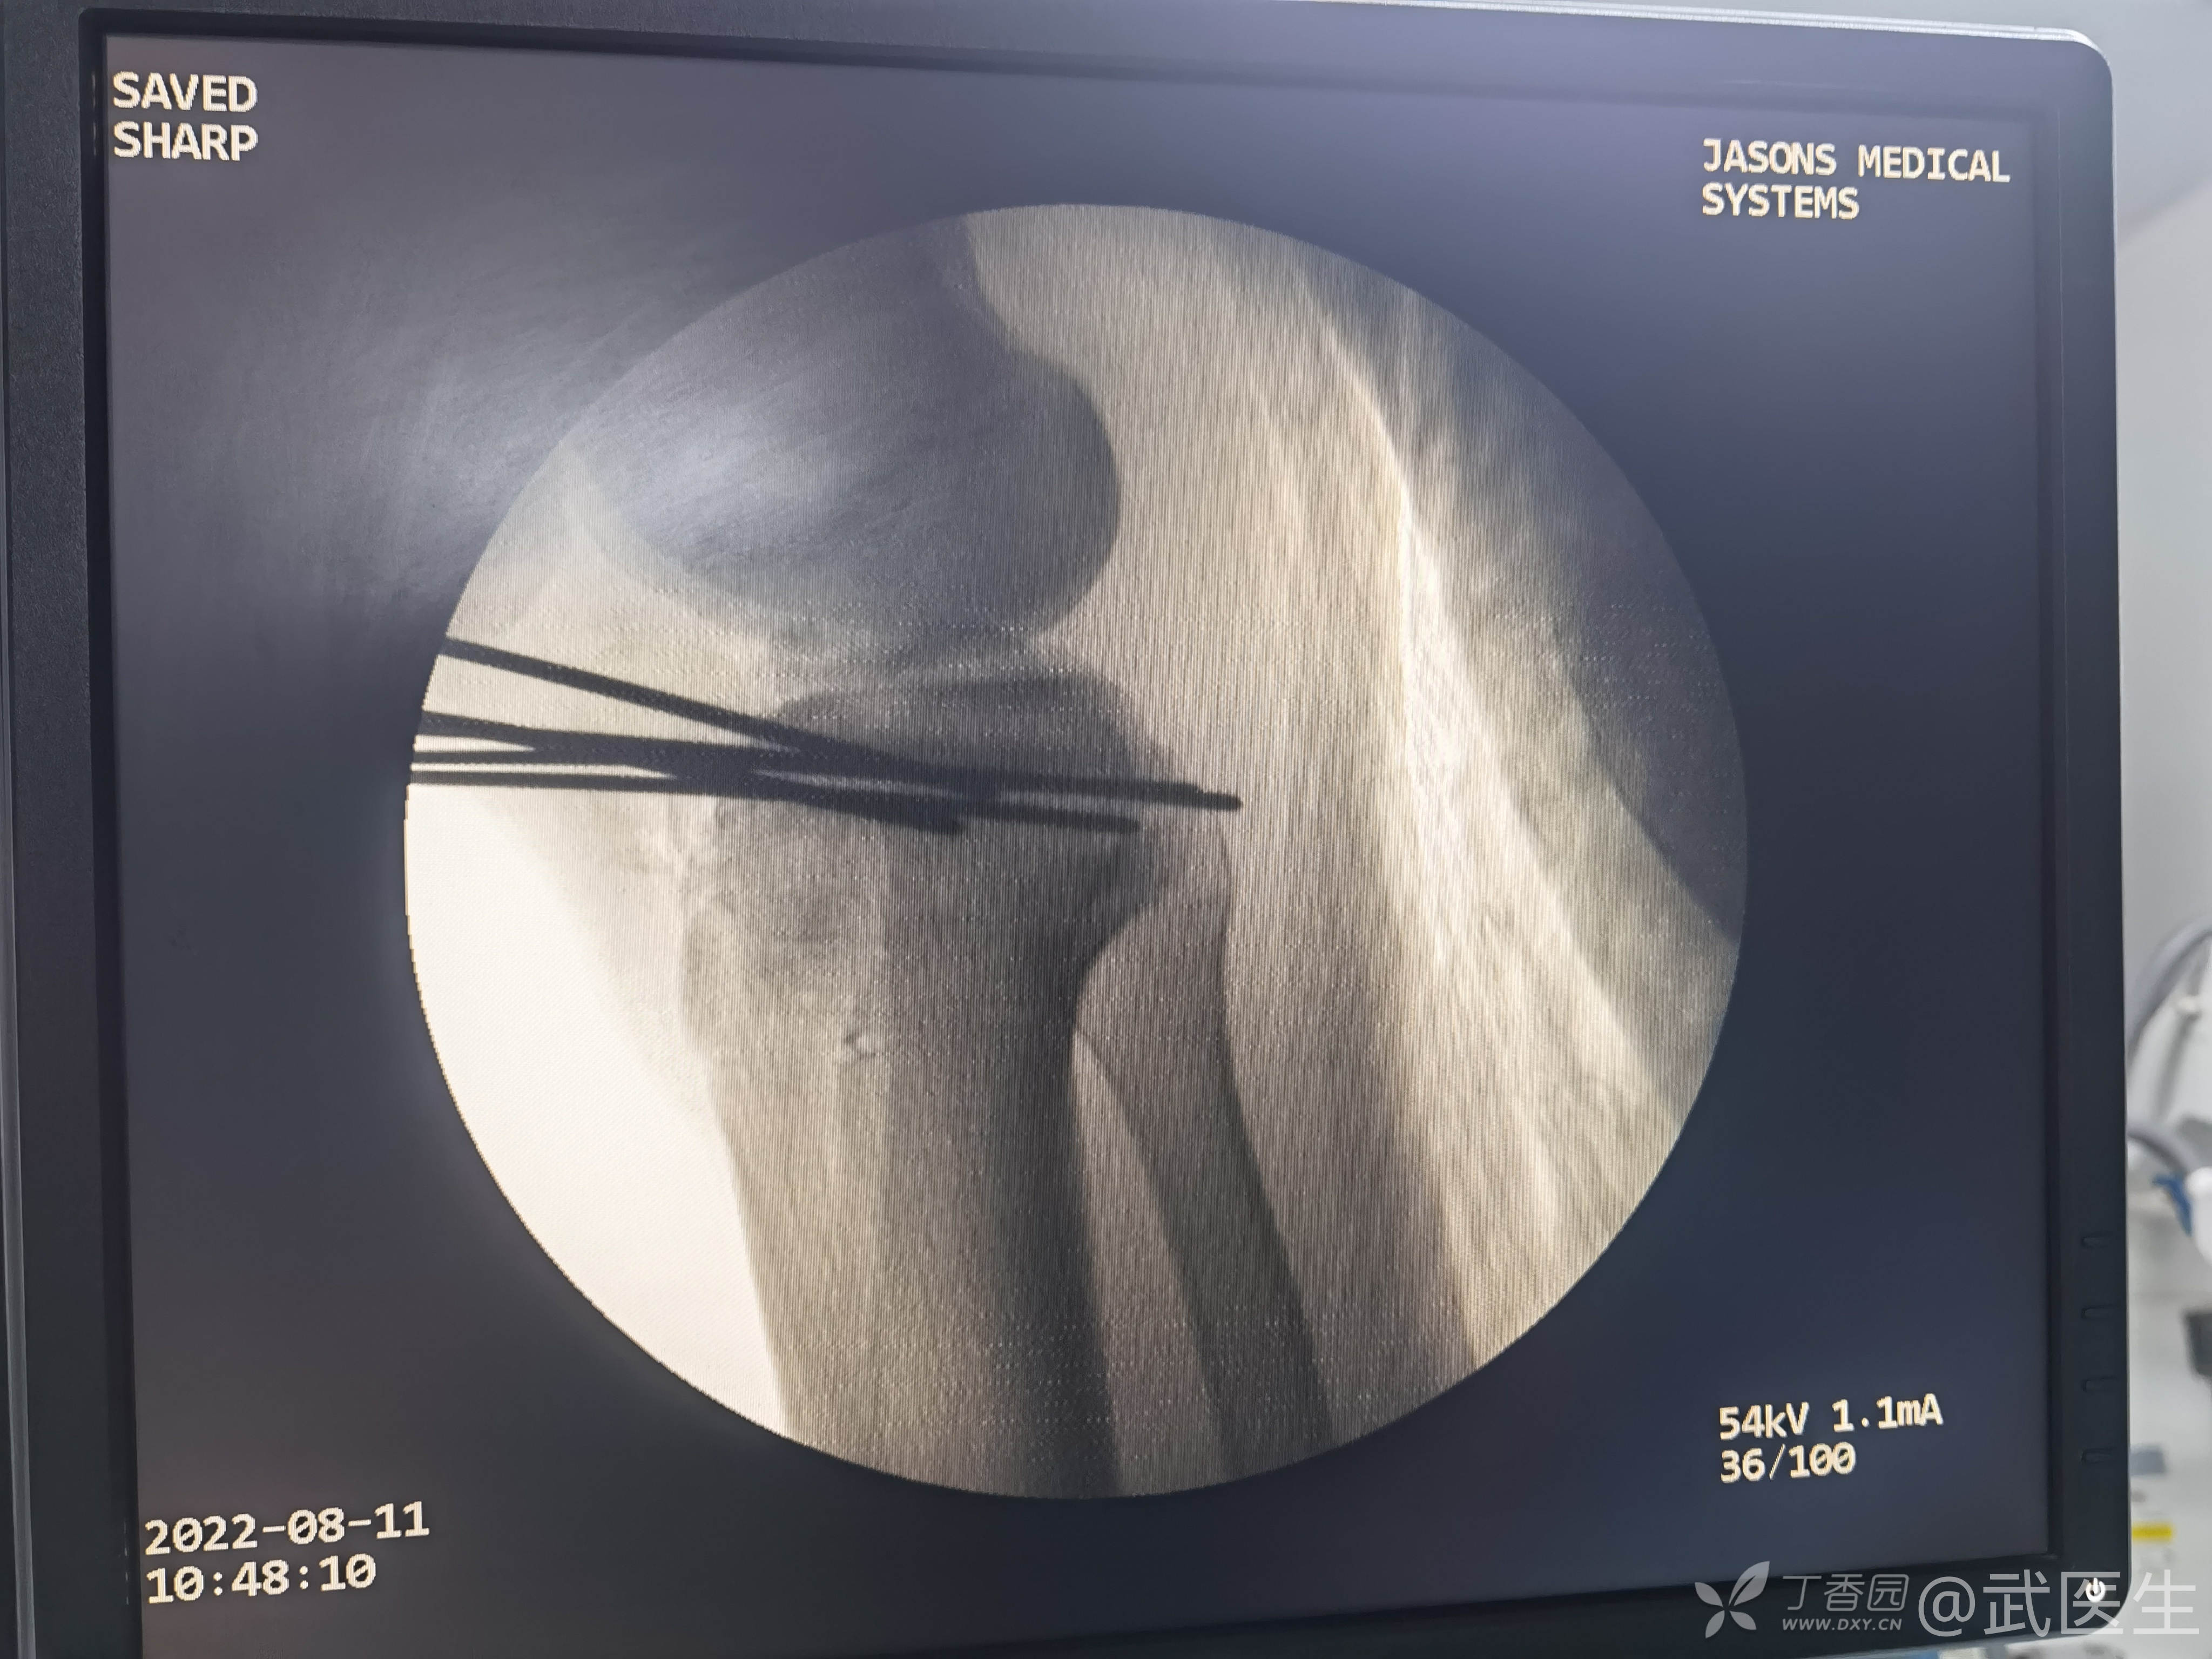

出现了题目中的一句话“但求義當先”,清理异物后创面VSD覆盖,择期骨折内固定

15岁,骨骺存在,关节加压固定,外侧板支撑